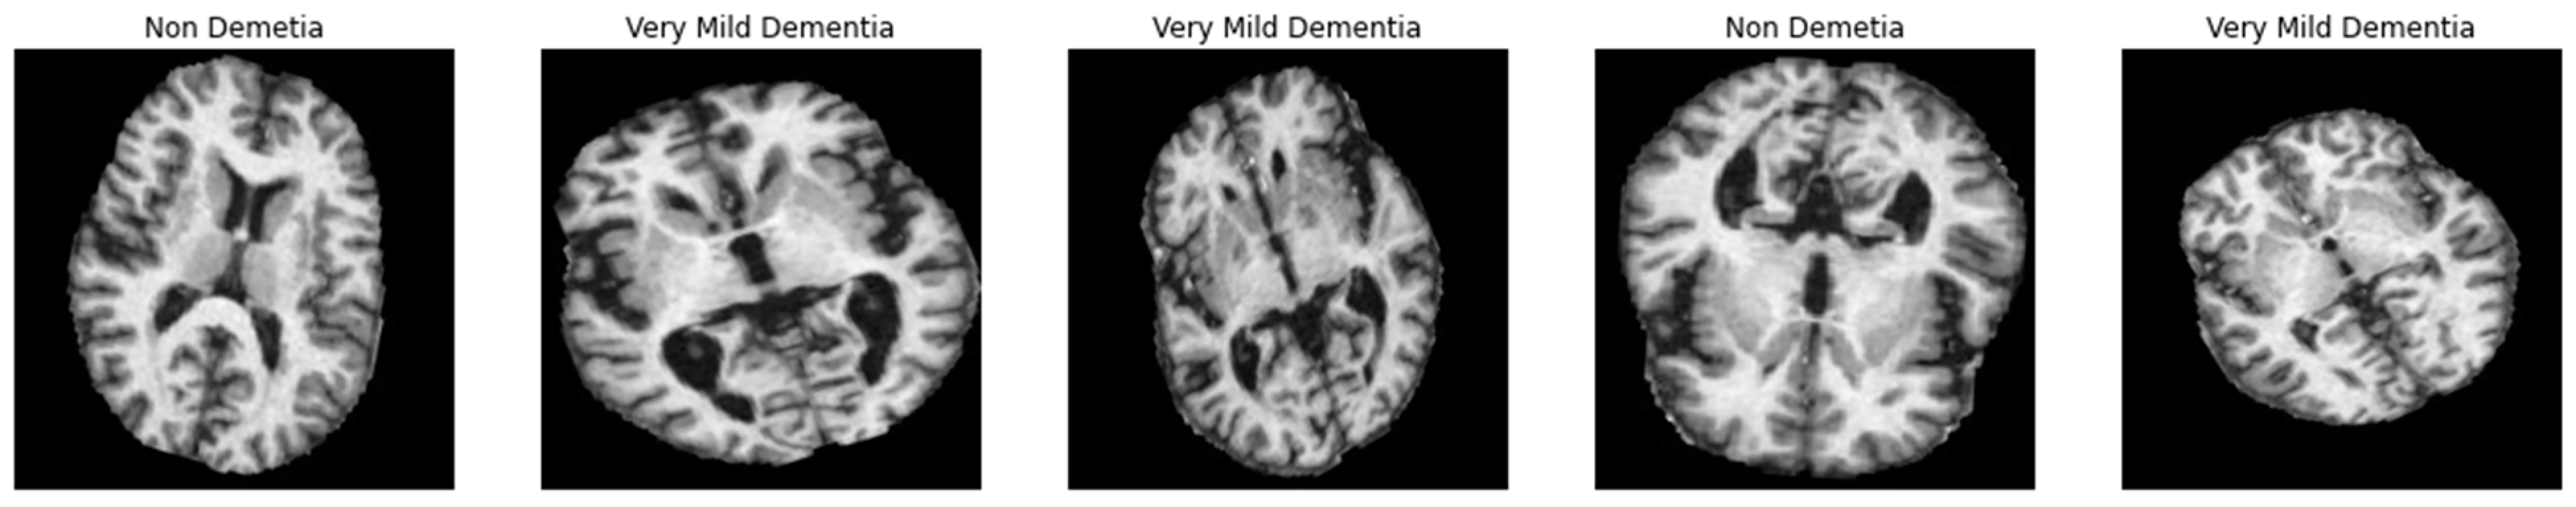

Figure 2.

A visual example of the proposed preprocessing step to enhance the contrast of MRI images, where figure (a,c) are the original and (b,d) are with noise removed and enhanced.